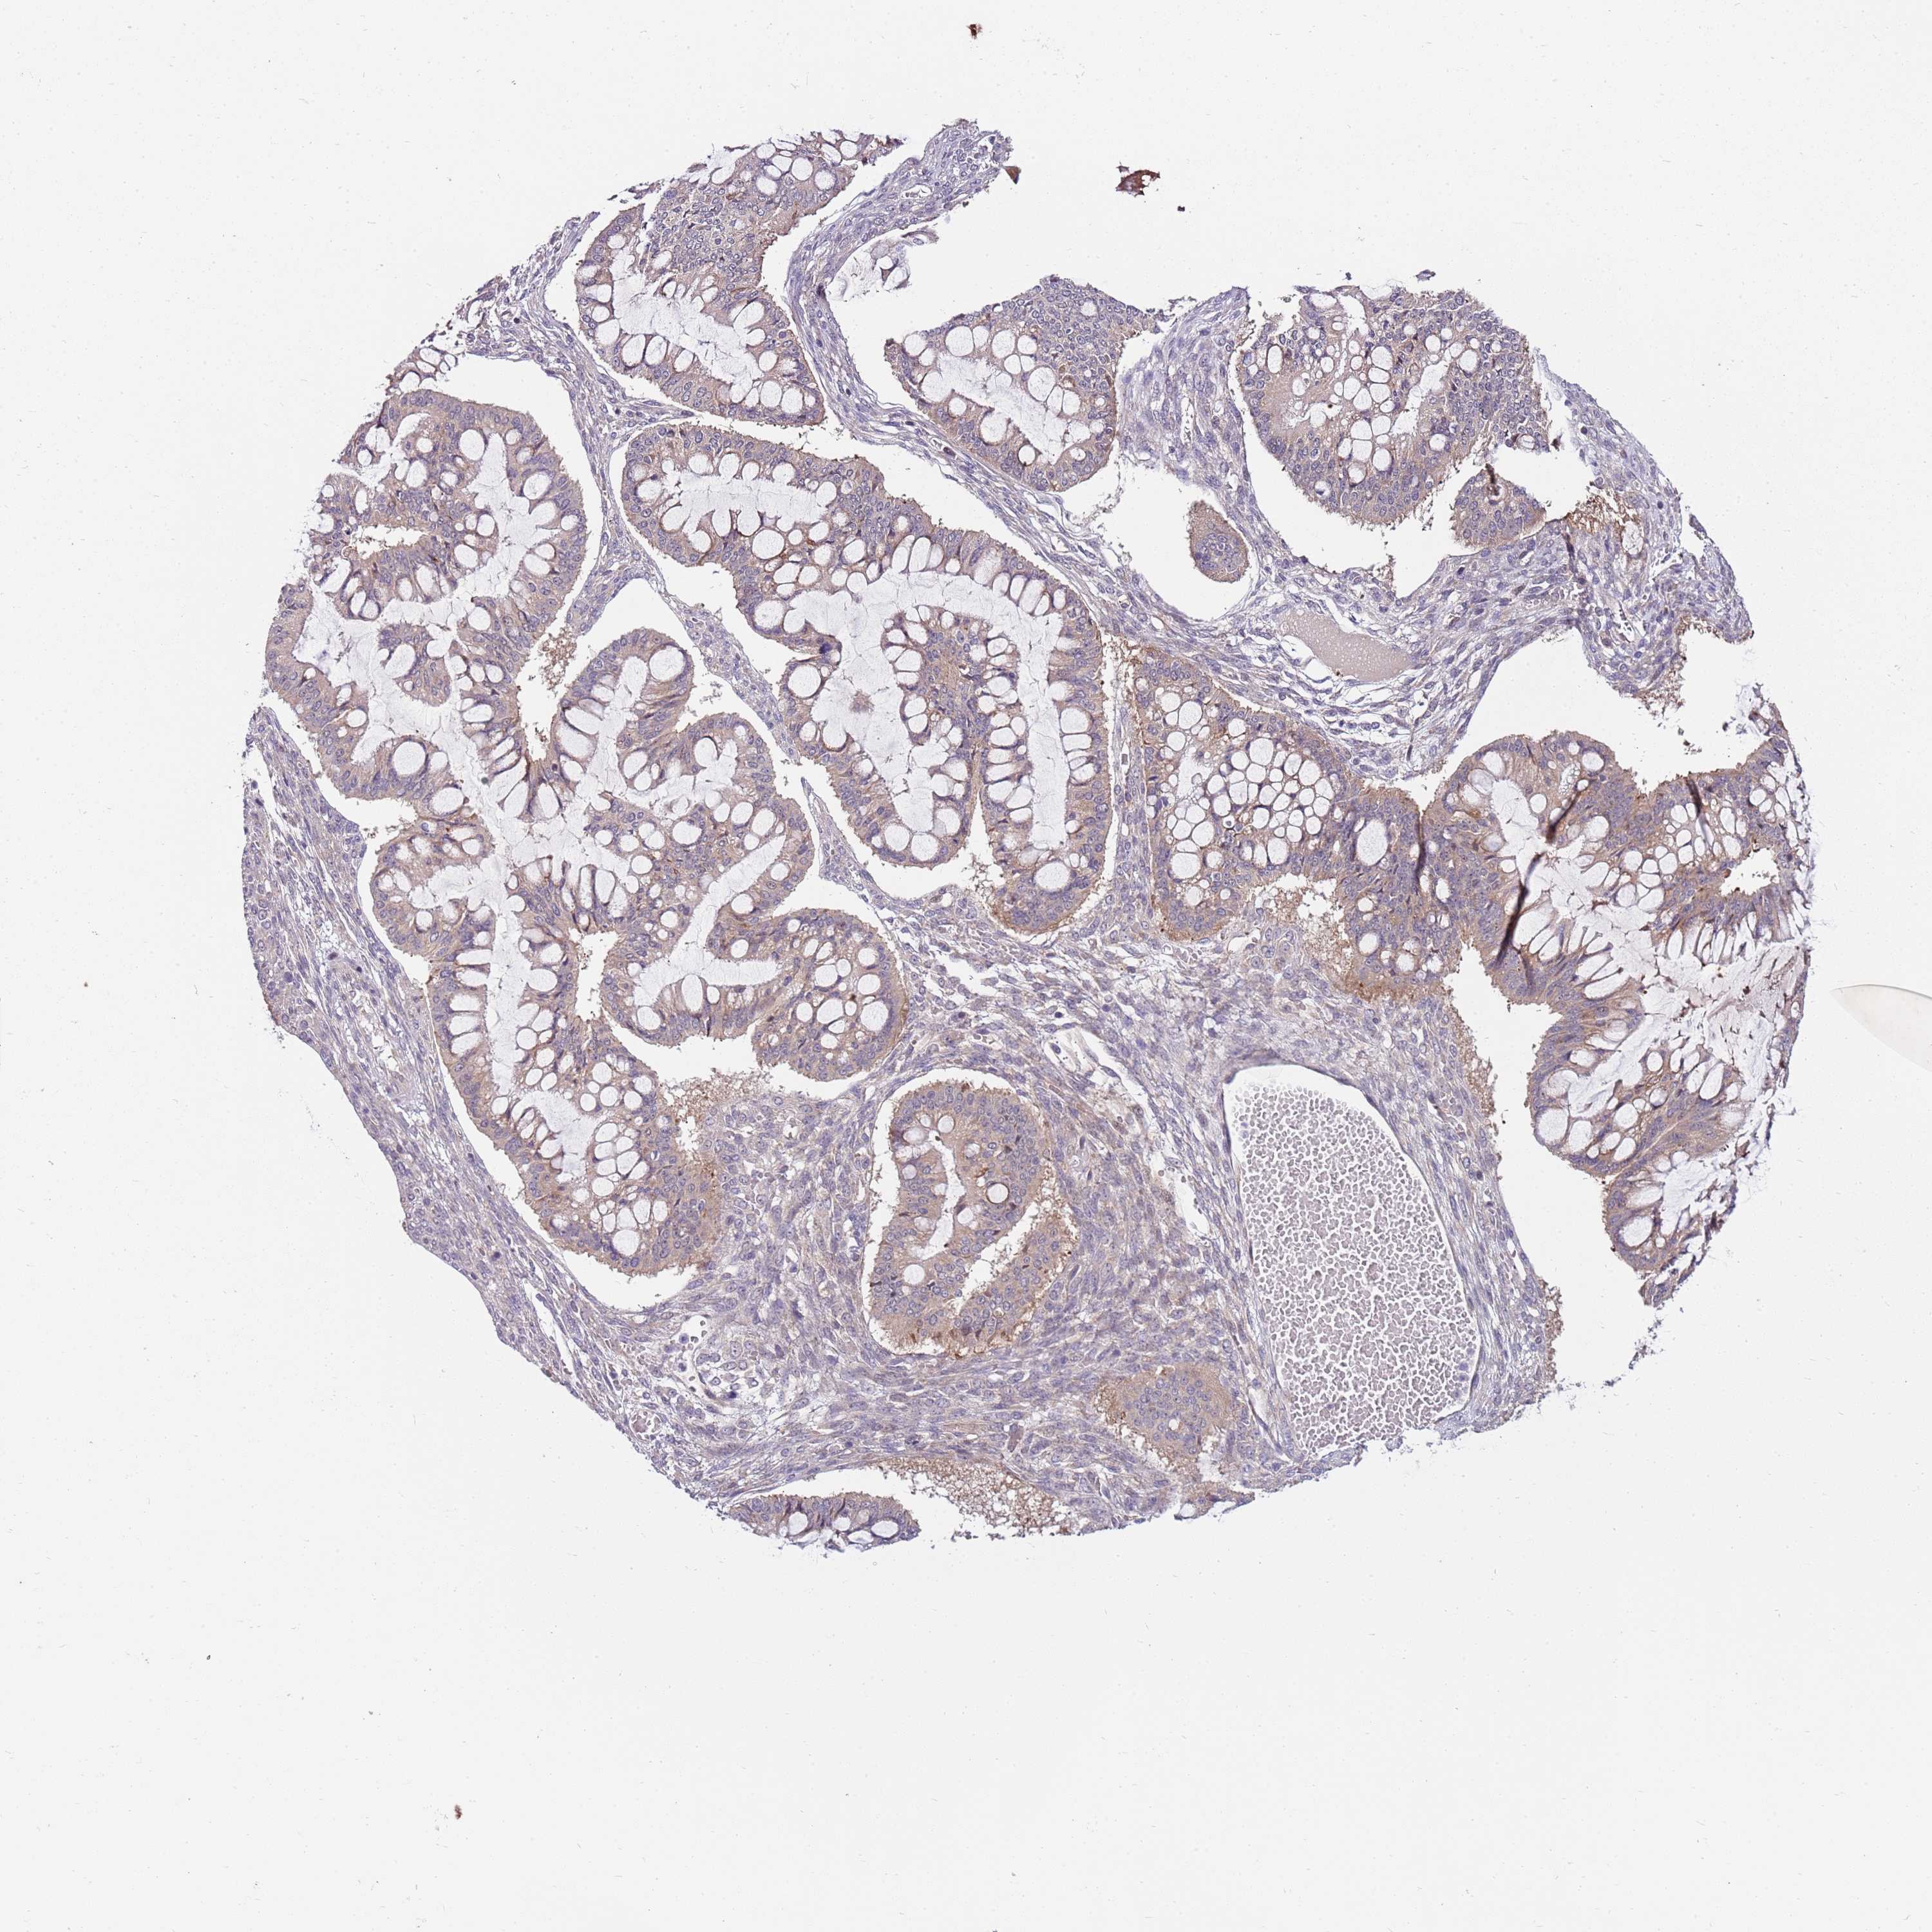

OVARIAN CANCER - Protein expressioni

A mouse-over function shows sample information and annotation data. Click on an image to view it in a full screen mode. Samples can be filtered based on level of antibody staining by selecting one or several of the following categories: high, medium, low and not detected. The assay and annotation is described here.

Note that samples used for immunohistochemistry by the Human Protein Atlas do not correspond to samples in the TCGA dataset.

Antibody stainingi

Antibody staining in the annotated cell types in the current human tissue is reported as not detected, low, medium, or high, based on conventional immunohistochemistry profiling in selected tissues. This score is based on the combination of the staining intensity and fraction of stained cells.

Each image is clickable and will lead to virtual microscopy that enables deeper exploration of all samples and also displays staining intensity scores, fraction scores and subcellular localization as well as patient and tissue information for each sample.

Antibody HPA047624

Antibody HPA054627

Cystadenocarcinoma, serous, NOS

Carcinoma, NOS

Cystadenocarcinoma, mucinous, NOS

Carcinoma, endometroid